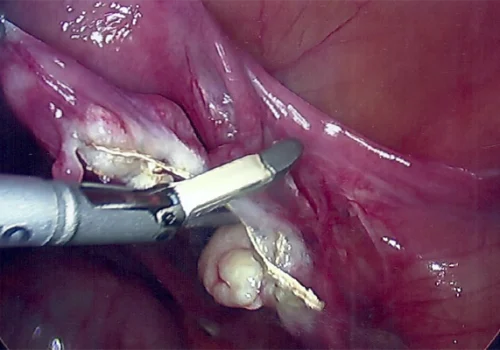

Procedure

She subsequently underwent Total Laparoscopic Hysterectomy and removal of both Tubes and Ovaries.